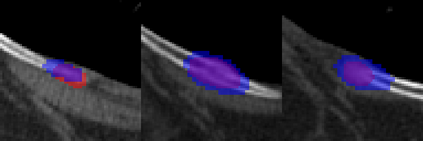

Rib fractures are a common and potentially severe injury that can be challenging and labor-intensive to detect in CT scans. While there have been efforts to address this field, the lack of large-scale annotated datasets and evaluation benchmarks has hindered the development and validation of deep learning algorithms. To address this issue, the RibFrac Challenge was introduced, providing a benchmark dataset of over 5,000 rib fractures from 660 CT scans, with voxel-level instance mask annotations and diagnosis labels for four clinical categories (buckle, nondisplaced, displaced, or segmental). The challenge includes two tracks: a detection (instance segmentation) track evaluated by an FROC-style metric and a classification track evaluated by an F1-style metric. During the MICCAI 2020 challenge period, 243 results were evaluated, and seven teams were invited to participate in the challenge summary. The analysis revealed that several top rib fracture detection solutions achieved performance comparable or even better than human experts. Nevertheless, the current rib fracture classification solutions are hardly clinically applicable, which can be an interesting area in the future. As an active benchmark and research resource, the data and online evaluation of the RibFrac Challenge are available at the challenge website. As an independent contribution, we have also extended our previous internal baseline by incorporating recent advancements in large-scale pretrained networks and point-based rib segmentation techniques. The resulting FracNet+ demonstrates competitive performance in rib fracture detection, which lays a foundation for further research and development in AI-assisted rib fracture detection and diagnosis.